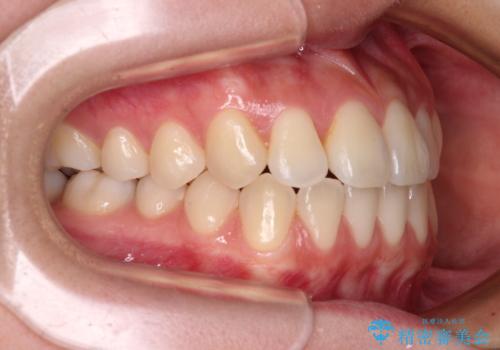

- 前歯のクロスバイトが気になり、インビザラインによる矯正治療を希望して来院された患者様です。

上顎側切歯(上の真ん中から2番目の歯)が舌側転位している場合、インビザラインでは仕上げきれないことが多く、更には無理して動かそうとすると歯髄壊死を起こすリスクが高いと言われています。

インビザラインで歯列を移動する前に、上顎前歯をワイヤー矯正で整え、その後上下歯列をインビザラインにて矯正治療を行うこととしました。

舌側転位している側切歯特有の、切縁の位置が不揃いであったり、根元が内側に引っ込んだ状態であったりという、インビザライン独特の仕上がりになることなく、きれいに整った歯列とすることができました。